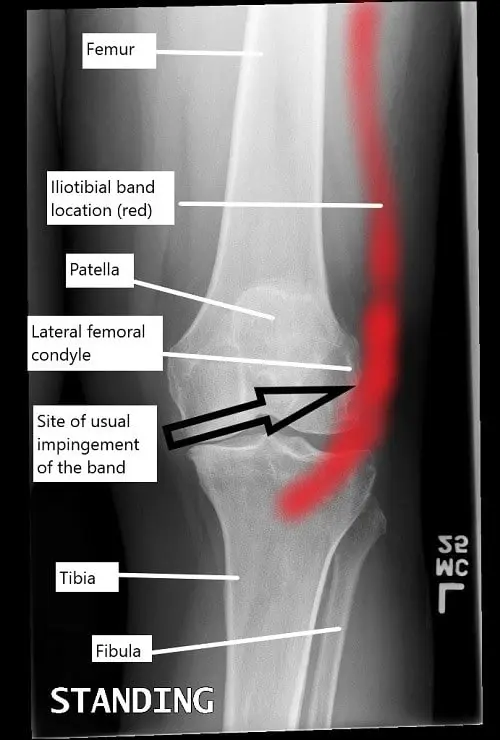

A knee x-ray illustrating the location of iliotibial band and the usual site of impingement.

The iliotibial band is a fibrous band that runs along the outer side of the thigh, extending from the hip to the shinbone. It connects the tensor fascia lata and gluteus maximus muscles to the tibia. The ITB helps stabilize the knee during activities such as walking, running, and cycling. Normally, the ITB moves smoothly over the lateral femoral condyle as the knee bends and straightens. However, when the ITB becomes tight or irritated, it can rub against the femoral condyle, leading to inflammation and pain.